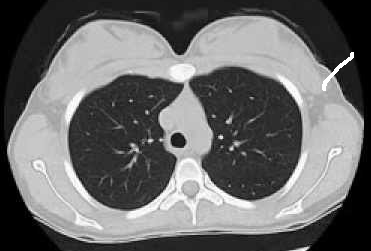

Run the model on a scan

Upload your own CT slice, or click any patient below to instantly see the model classify a real scan.

Try a real scan— click any patient to run inference instantly

INPUT

OUTPUT